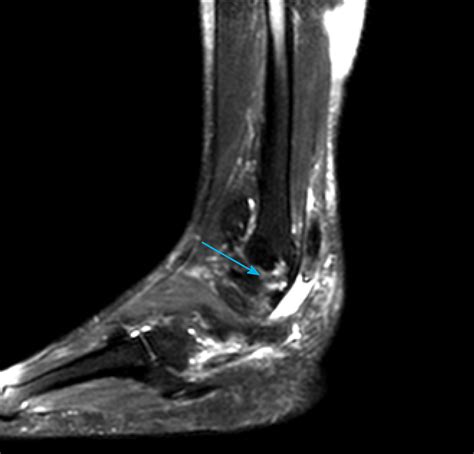

• MRI (Magnetic Resonance Imaging): This is the gold standard for visualizing soft tissue. It provides high-resolution images that clearly show tears, inflammation, or degeneration within the tendon.